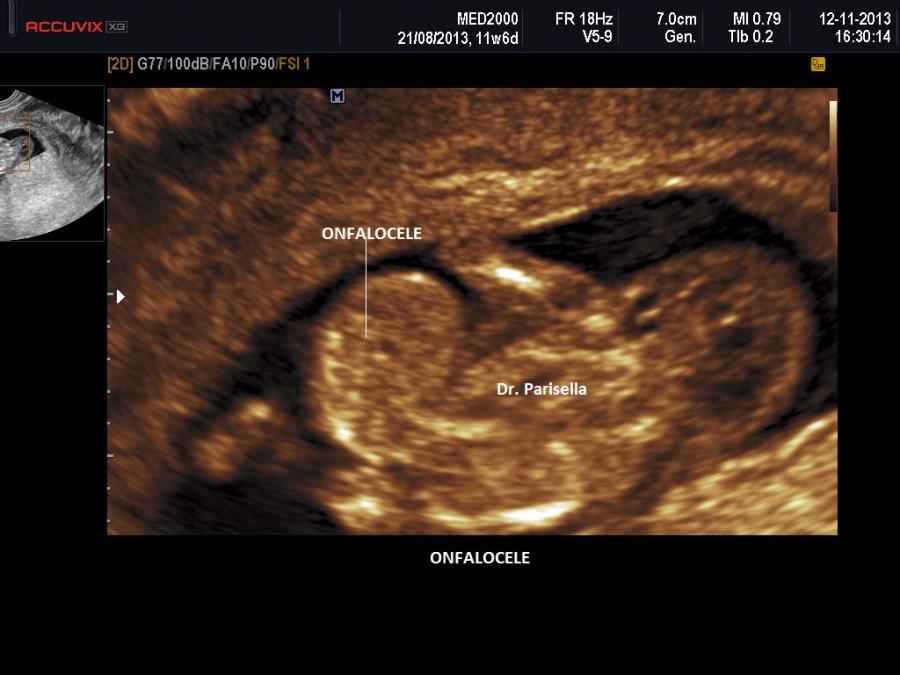

La Sindrome di Gershoni-Baruch รจ una rara malformazione congenita multipla caratterizzata da onfalocele, ernia diaframmatica, anomalie cardiovascolari e difetti radiali.